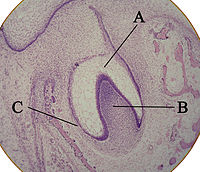

The tooth bud (sometimes called the tooth germ) is an aggregation of cells that eventually forms a tooth. These cells are derived from the ectoderm of the first branchial arch and the ectomesenchyme of the neural crest. The tooth bud is organized into three parts: the enamel organ, the dental papilla and the dental follicle.

The enamel organ is composed of the outer enamel epithelium, inner enamel epithelium, stellate reticulum and stratum intermedium. These cells give rise to ameloblasts, which produce enamel and the reduced enamel epithelium. The location where the outer enamel epithelium and inner enamel epithelium join is called the cervical loop. The growth of cervical loop cells into the deeper tissues forms Hertwig's Epithelial Root Sheath, which determines the root shape of the tooth.

The dental papilla contains cells that develop into odontoblasts, which are dentin-forming cells. Additionally, the junction between the dental papilla and inner enamel epithelium determines the crown shape of a tooth. Mesenchymal cells within the dental papilla are responsible for formation of tooth pulp.

The dental follicle gives rise to three important entities: cementoblasts, osteoblasts, and fibroblasts. Cementoblasts form the cementum of a tooth. Osteoblasts give rise to the alveolar bone around the roots of teeth. Fibroblasts develop the periodontal ligaments which connect teeth to the alveolar bone through cementum.